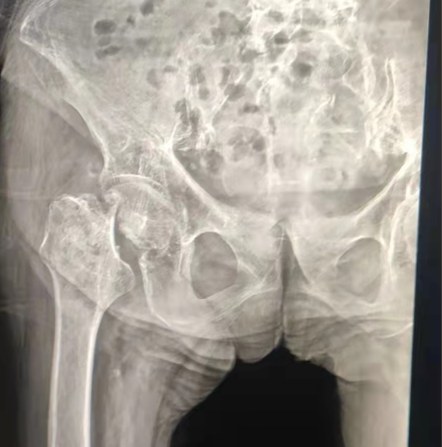

Partage de cas | Un patient de 70 ans, a reçu le remplacement total de la hanche avec le système de hanche cimenté par Lepu

Système cimenté de hanche:

Matériaux d'alliage de Co-Cr-Mo

Haute résistance à l'usure

Grande résistance mécanique

Conception de fil d'épaule

Facilement installer, tenir et ajuster l'angle

Traitement de surface poli

Pour obtenir une excellente croissance osseAssurer la stabilité de la fixation précoce

12/14 Conception standard de chandelle

Proximal Mix Anatomy

Design Collection Europe et USA Caractéristiques de la tige

Traitement distal de coupe d'Adge des deux côtés

Réduire la pression dans la cavité médullaire